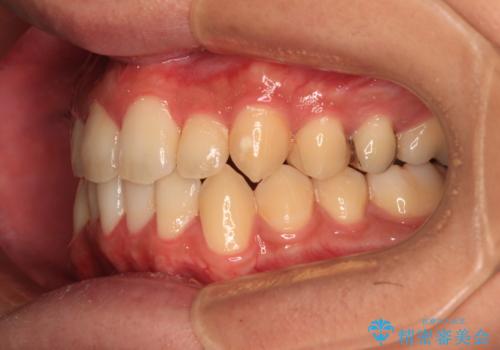

前歯のクロスバイト インビザラインによる矯正治療

- 上下のクロスバイトと前歯のデコボコを気にして来院された患者様です。

インビザラインを用い、IPR(歯と歯の間を削る)と歯列全体を拡大させることで、歯並びを整えていくこととしました。

インビザライン特有の、治療後半に奥歯が咬み合わないという事象が長引きました。

咬み合わないときの対処方法は色々とありますが、ゴムかけなどを活用して噛めるようにしました。